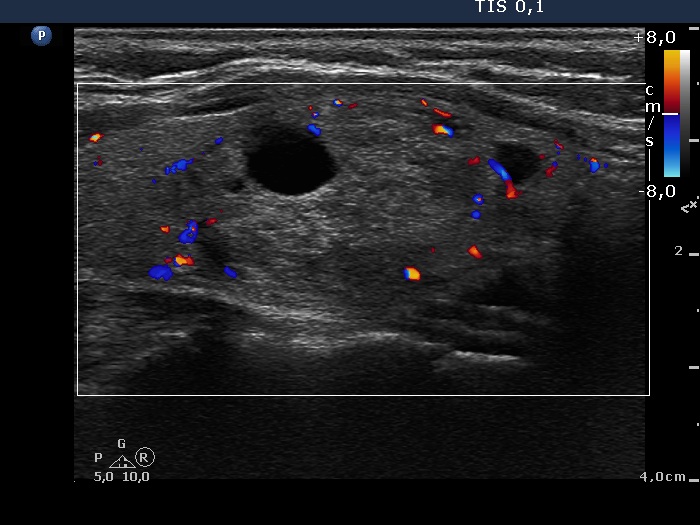

Left lobe, longitudinal scan, color Doppler mode. The large nodule displays signs of a type 2 vascular pattern.